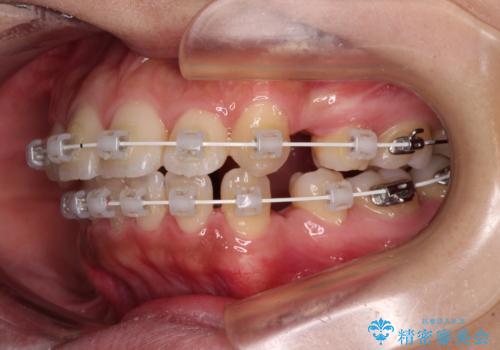

- 矯正装置

- 審美装置

- 治療期間

- 2年1ヶ月

- 治療回数

- 10-30回